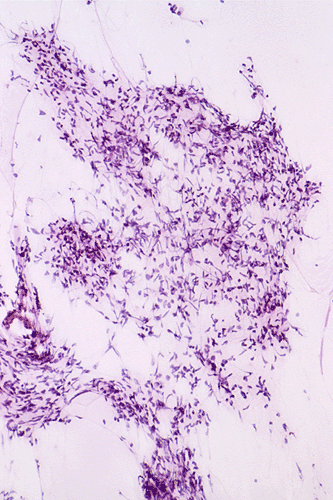

The following photos are taken from representative areas. Panel A and B are taken from intro-operative cytologic preparation. Panel C to F are taken from the frozen section. Panel G to I are taken from formalin fixed paraffin embedded material that has not been frozen. Panel J is fluorescent in situ hybridization (FISH) studies on epidermal growth factor receptor (EGFR).

A. B. C. D. E. F.

G. H. I. J.

Intraoperative consultation: The cytologic preparation provides some very useful information. The cells form poorly defined clumps with elongated, pale pink cytoplasmic processes (Panel A, arrow). The nuclei are elongated, hyperchromatic and resemble "baking potato". Nucleoli are not seen  (Panel B), On the frozen section, a small streak of pale pink tissue suggestive of necrosis is present (Panel C and D). On high-magnification, the viable tumor cells have medium to large amount of cytoplasm and without distinct cytoplasmic border. They are densely packed, with hyperchromatic nuclei and does not form a specific pattern (Panel E). The interphase between the necrotic cells and the viable cells on frozen section is illustrated in (Panel F). The intraoperative diagnosis was "high-grade glial neoplasm with necrosis, probably glioblastoma".